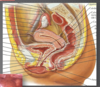

Lien entre les organes gynéco et la vessie

- Vessie en contact direct avec portion proximale du vagin antérieur

- Séparée de l’utérus par le péritoine vésico-utérin

- Vessie s’affaisse lorsque vide

Lien entre les organes gynéco et l’uretère

1- Derrière les vaisseaux ovariens

2- Au-dessus des vaisseaux iliaques au niveau de la bifurcation iliaque

3- Passe sous l’artère utérine (à 1-2 cm du col): Est Perpendiculaire au ligament large à sa portion inférieure

4- Entre dans la vessie de chaque côté de la limite supérieure du trigone

Lien entre organes gynéco et rectum

- En étroite relation avec la paroi postérieure du vagin

- Séparée par le septum recto-vaginal et le cul-de-sac rectovaginal de Douglas

Lien entre organes gynéco et colon

- Le colon sigmoïde contourne l’annexe gauche: De supéro-latéral vers inféro-médian

- Le caecum et l’appendice sont près de l’annexe droite: En supéro-latéral (droit)